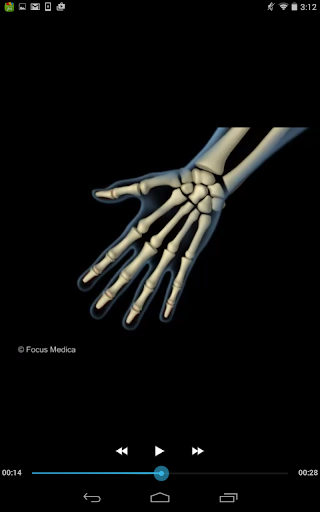

The FOCUS Animated Pocket Dictionary of RHEUMATOLOGY is the first ever animated dictionary in the subject. A valuable reference for physicians and students alike, it covers 100 rheumatology related terms and definitions. All the definitions have been graphically described with the help of 3D animations and are accompanied by text definitions.

The Focus Animated Pocket Dictionaries are the world’s first ever animated dictionaries that provide definitions of medical terms with the aid of realistic and narrated 3D animations, complimented with text definitions. Terms arranged alphabetically making definitions easy to search. These unique visual dictionaries are excellent reference sources for health professionals, students and health consumers. The videos play independent of the internet once downloaded.